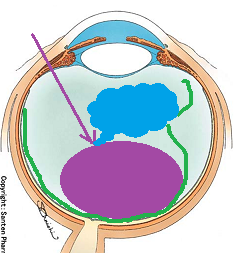

黒目(角膜)から入ってきた光は、目の奥の方のフィルム(網膜)に当たります。網膜は一つの束(視神経)になって、最終的には脳ミソにつながり、「物が見える」という事になります。

図の赤矢印の部分は視神経乳頭と言って、網膜が集まって束になる部分なのですが、実はこの部位のみ光を感じ取ることはできないのです。

写真だと水色の部分が視神経乳頭(マ盲点)になります。ちなみに、物を見る中心部の網膜は黄斑と呼ばれ、オレンジの矢印に当たります。